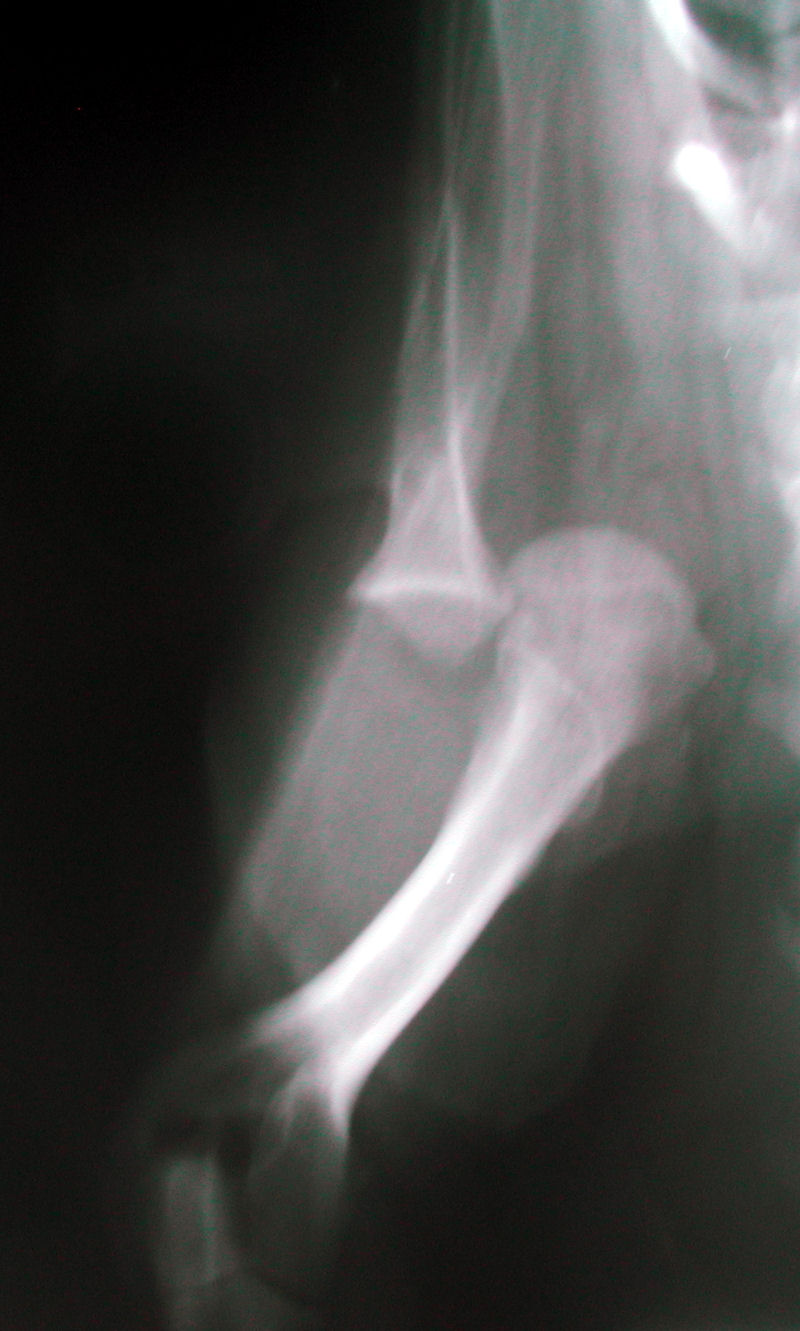

Shoulder luxation 02 radiography mediolateral in Dogs (Canis Dog Twisted Shoulder The gait of a dog having shoulder instability is usually abnormal at the walk and the trot. Dogs can be boisterous, playful, and very active, so it’s not surprising that they sometimes end up with injuries during all the rough and tumble. As well as pulled leg muscles, it is also possible for dogs to injure their shoulders. There are. Dog Twisted Shoulder.